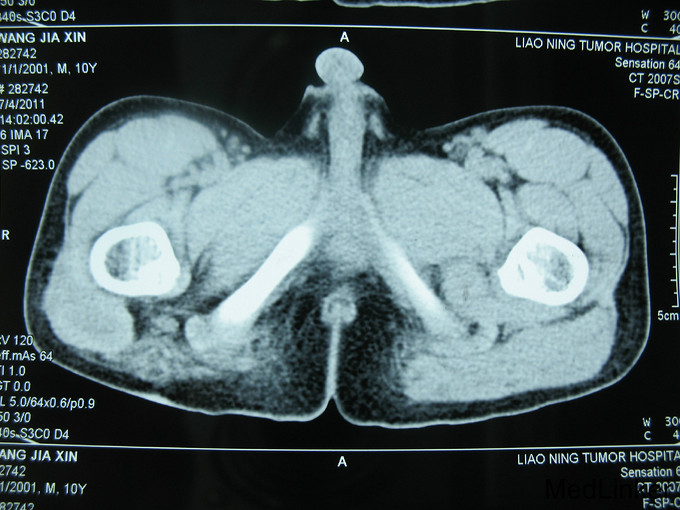

右臀肿物术后4年,复发1个月 患者4年前右臀部有一肿物手拳大小,于当地医手术治疗,术后病理自述为纤维瘤。术后无特殊治疗,1个月前手术区再次发现肿物,增长迅速。

右臀部手术区可见15cm长的手术瘢痕,瘢痕下可 及硬韧肿物大小约10x7cm,边界不清,活动度差。

侵袭性纤维瘤病是一种不明原因、不发生转移的成纤维细胞性瘤样肿物。起源于肢体和韧带的肌筋膜结构,累及骨骼肌腱膜和筋膜,并对周围组织产生压迫。病变很易局部复发,并呈侵袭性生长,最常见于青年人的肩胛带、股部及臀部。侵袭性纤维瘤术后复发几率高,对周围组织侵袭性强。本例患者给予扩大切除术后随诊至今未发现复发病灶。